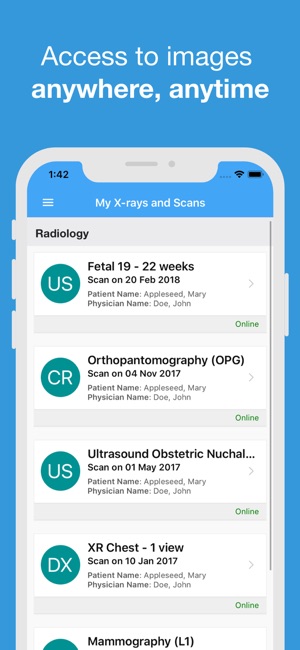

RadLink Patient Portal manages your personal radiology records with 24/7 secure online access from any computer, smartphone or tablet. This means when you visit an imaging centre that is under RadLink, you will be able to receive a permanent, digital copy of your imaging record and share easily with any healthcare professional. RadLink Patient Portal will help you to take a more active, informed role in managing your healthcare needs.